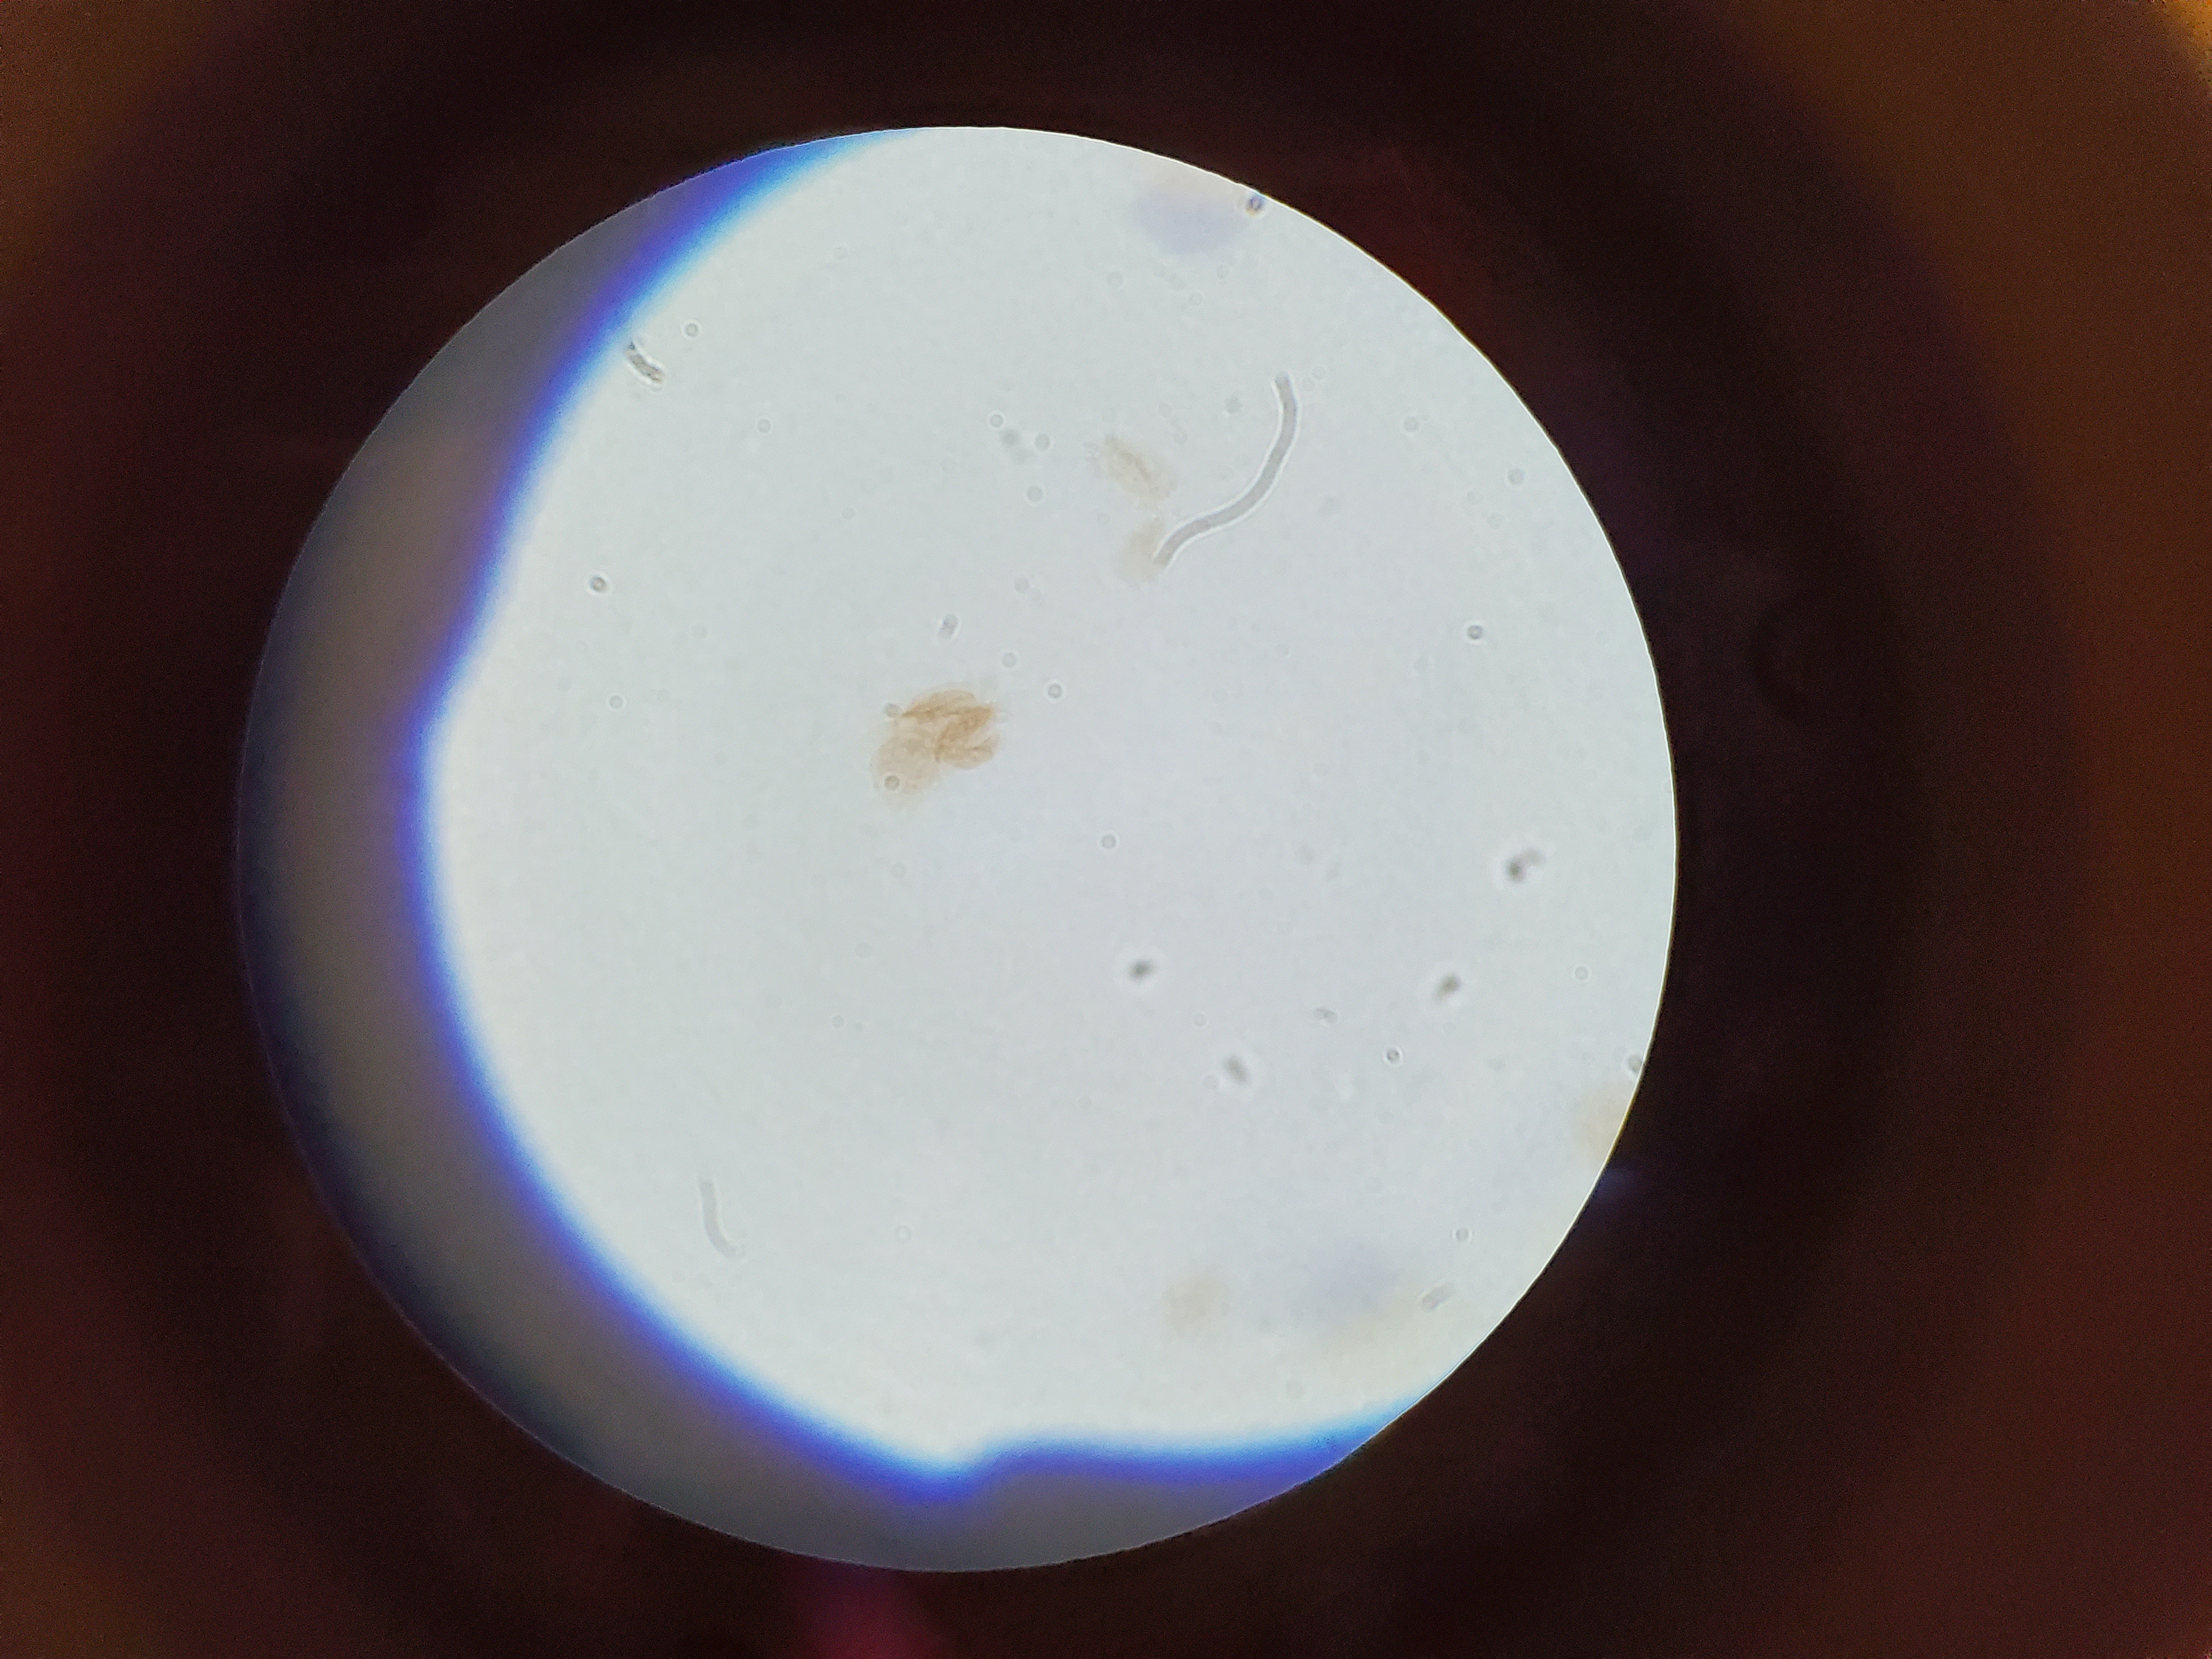

Ancylostoma caninum

Stage: Rhabditiform larva